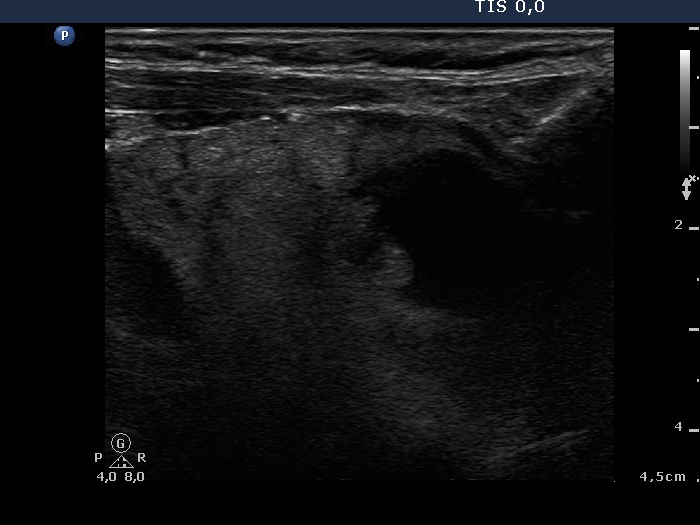

Lymph nodes - case conp 059 (ultrasonographic picture 2)

Right lobe, longitudinal view.